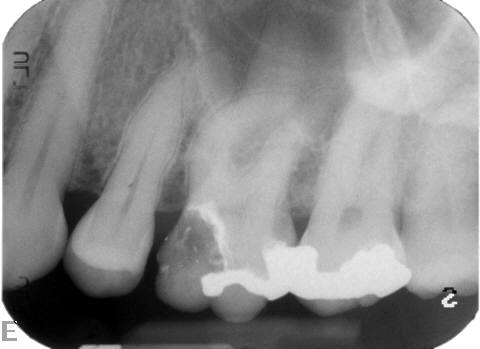

The master cone PA is the last indicator clinicians have in assessing whether or not their working lengths were truly accurate. This radiograph is crucial in affording the practitioner the opportunity to make adjustments to properly complete the procedure to the desirable lengths. An example is presented in Figure 15 through Figure 18. Figure 16 and Figure 17 show a master cone PA that demonstrates two of four canals to proper length. After adjusting the length of the other two master cones, the clinician was able to correct the lengths to produce a more appropriate result, as seen in Figure 18.

Fig 15. Molar with significant radiolucencies.

Figure 15

Fig 16. Mesial-lingual (ML) length looks to be precise, while distal-lingual (DL) looks to be slightly long.

Figure 16

Fig 17. Mesial-buccal (MB) length appears to be long, and distal-buccal (DB) has a kink likely due to its joining the DL canal just before the apex.

Figure 17

Fig 18. Completed case shows how the lengths were corrected prior to final obturation to achieve an ideal result.

Figure 18